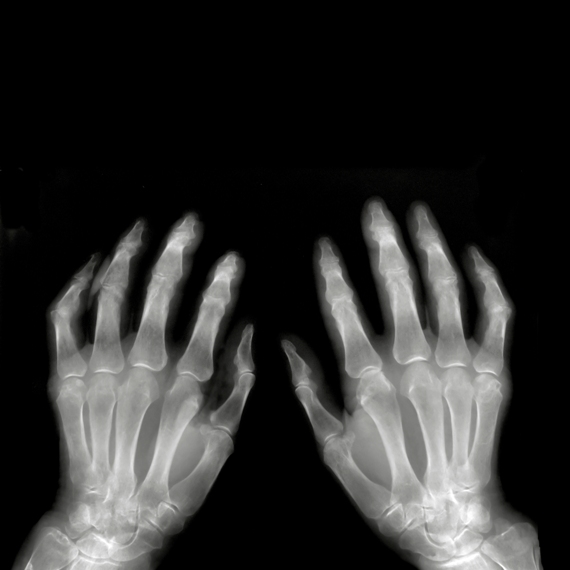

צילום כף היד

מאזין מודאג: "יש לי גירוד קבוע בכף היד"

מאזינה: "יש לי ג'ולה על כף היד והרופאים אומרים שאין מה לעשות - זה נכון?"